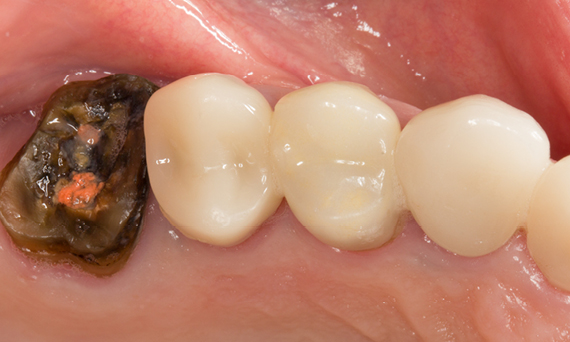

Rehabilitación del cuadrante

Dos coronas CEREC Tessera y dos inlays

En una sola visita de cuatro horas, se realizó la restauración de dos coronas y dos inlays, que tenían 15 años. El paciente quedó muy satisfecho con el muy buen resultado estético.

Antes: Obturaciones insuficientes en el segundo cuadrante. Las restauraciones tenían alrededor de 15 años.

Después: Coronas fabricadas chairside hechas de CEREC Tessera (dientes 26/27). Inlays para los dientes 24 y 25 hechas de bloques de composite.